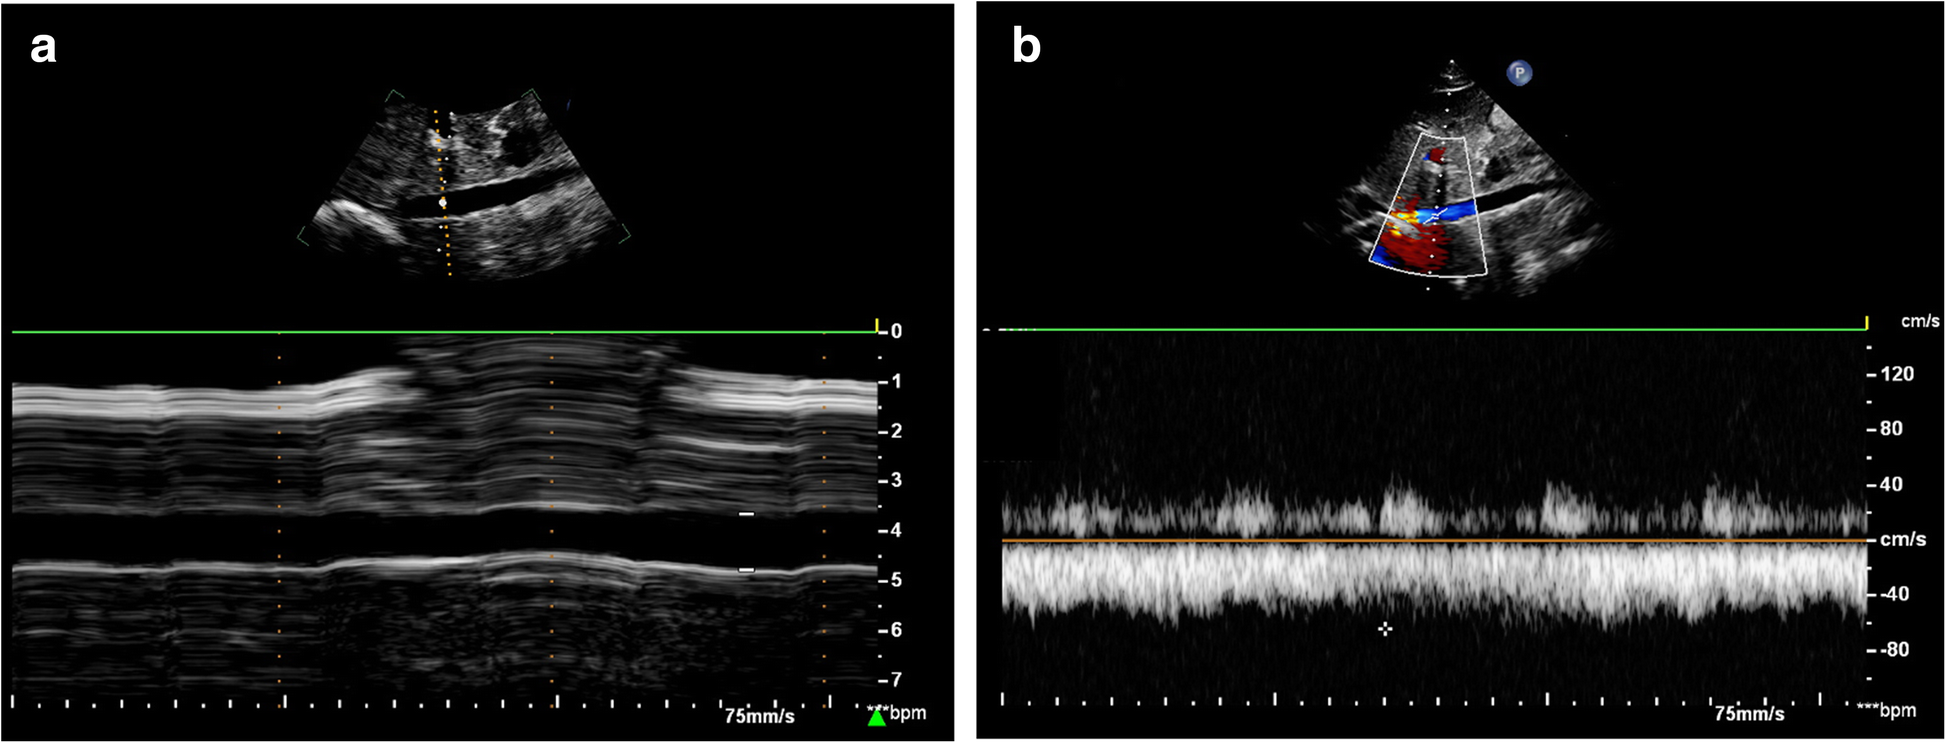

Fig. 2From: The transverse diameter of right common femoral vein by ultrasound in the supine position for predicting post-spinal hypotension during cesarean deliveryMeasurement of IVC by ultrasound with the cardiac probe. a M-mode image showing the anteroposterior diameter of IVC; b Pulsed-wave Doppler-mode image showing the peak velocity of IVC; IVC, inferior vena cavaBack to article page